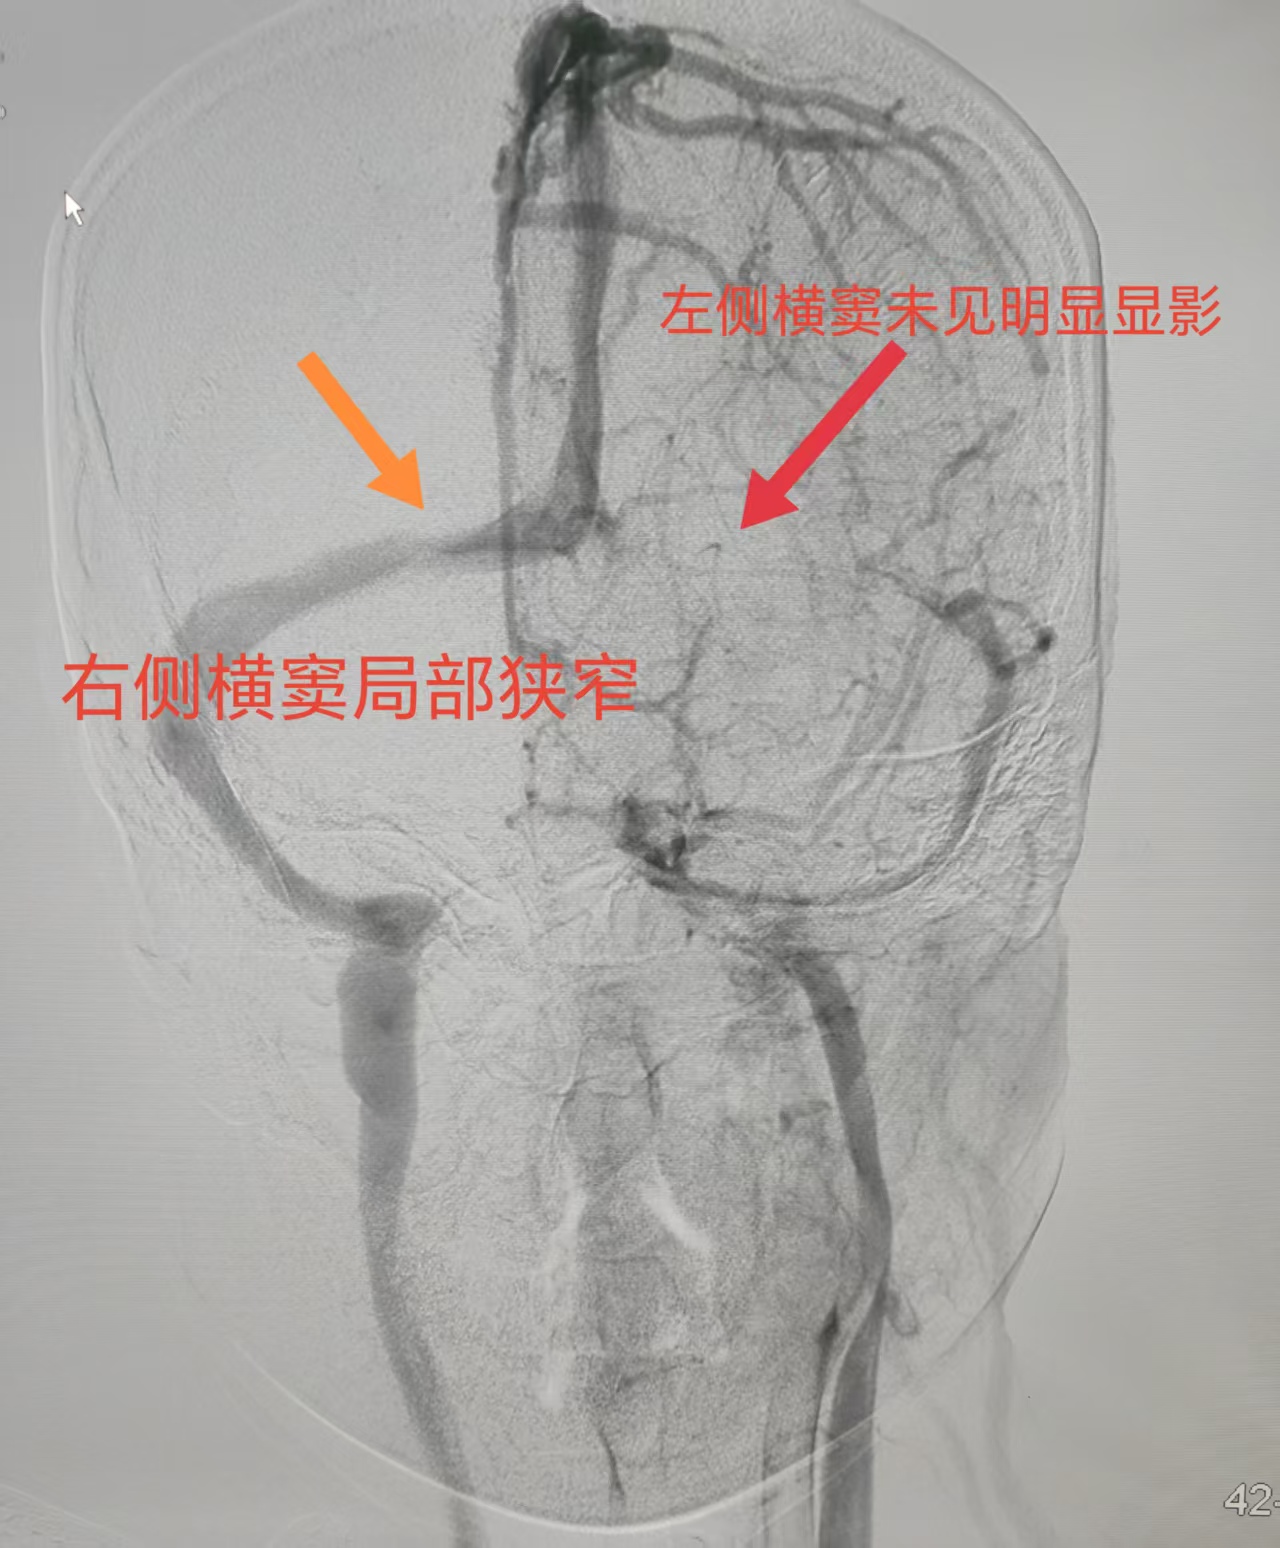

三年来,头痛如影随形地伴随着小荀,她试过各种药物和治疗,效果都不理想。王建峰主任团队接诊后,为她安排了系统检查。头颅MRV提示“左侧横窦未见显影,右侧横窦局部狭窄”,腰穿压力高达220mmH₂O,眼底检查也发现双侧视乳头水肿。这一系列线索都指向了一种极容易被忽视的疾病——特发性颅内压增高症,而静脉窦狭窄很可能是其背后的“真凶”。